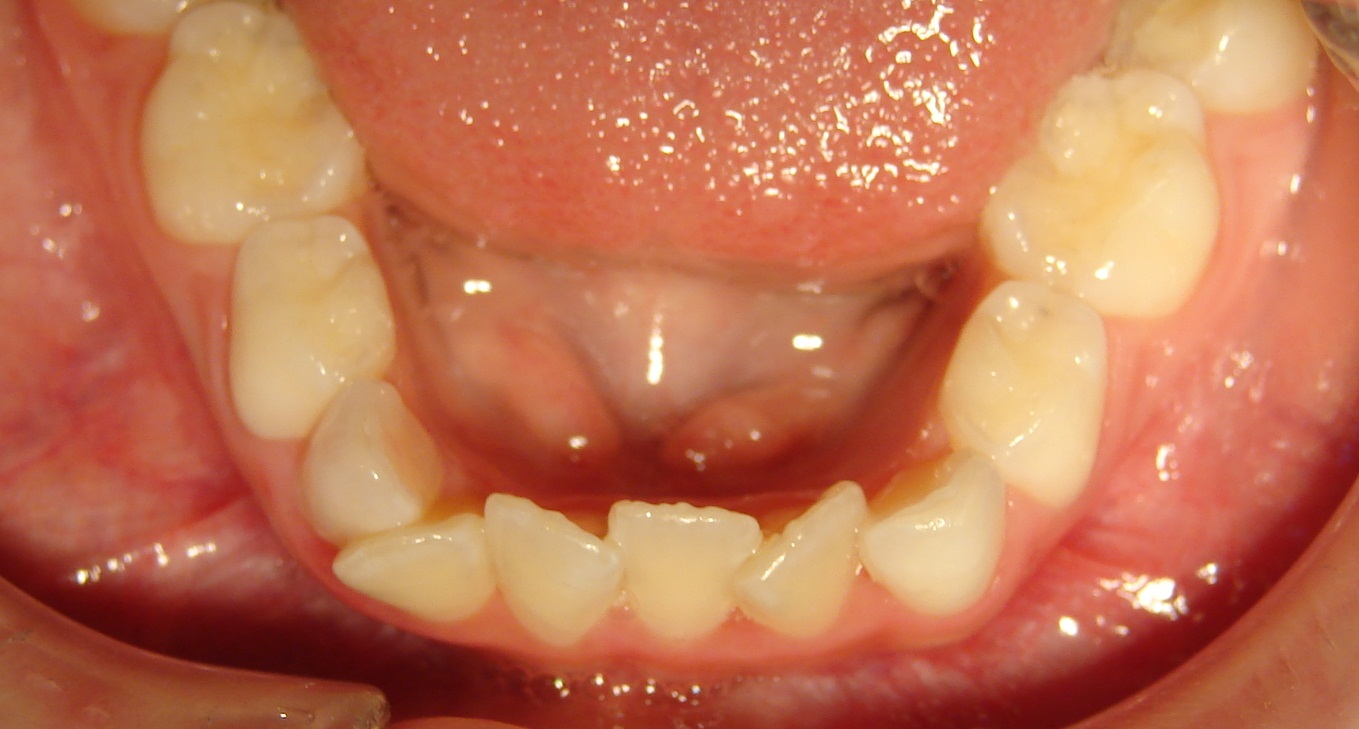

Apiñamiento dental

Este problema de mal posición dental lo vemos comúnmente cuando inicia la erupción de los primeros dientes permanentes, con los incisivos inferiores y posteriormente los superiores. En algunas ocasiones puede darse solo abajo, solo arriba o en ambos lados.

Esto ocurre porque los dientes permanentes vienen con mayor tamaño que los temporales o de leche y se rotan.

Los tratamientos o abordajes para ir solucionando estos problemas son varios, puede ir simplemente desde extraer algunos de los dientes de leche para que los permanentes se autocorrijan, colocar algún aparato removible o en casos más severos, colocar brackets.